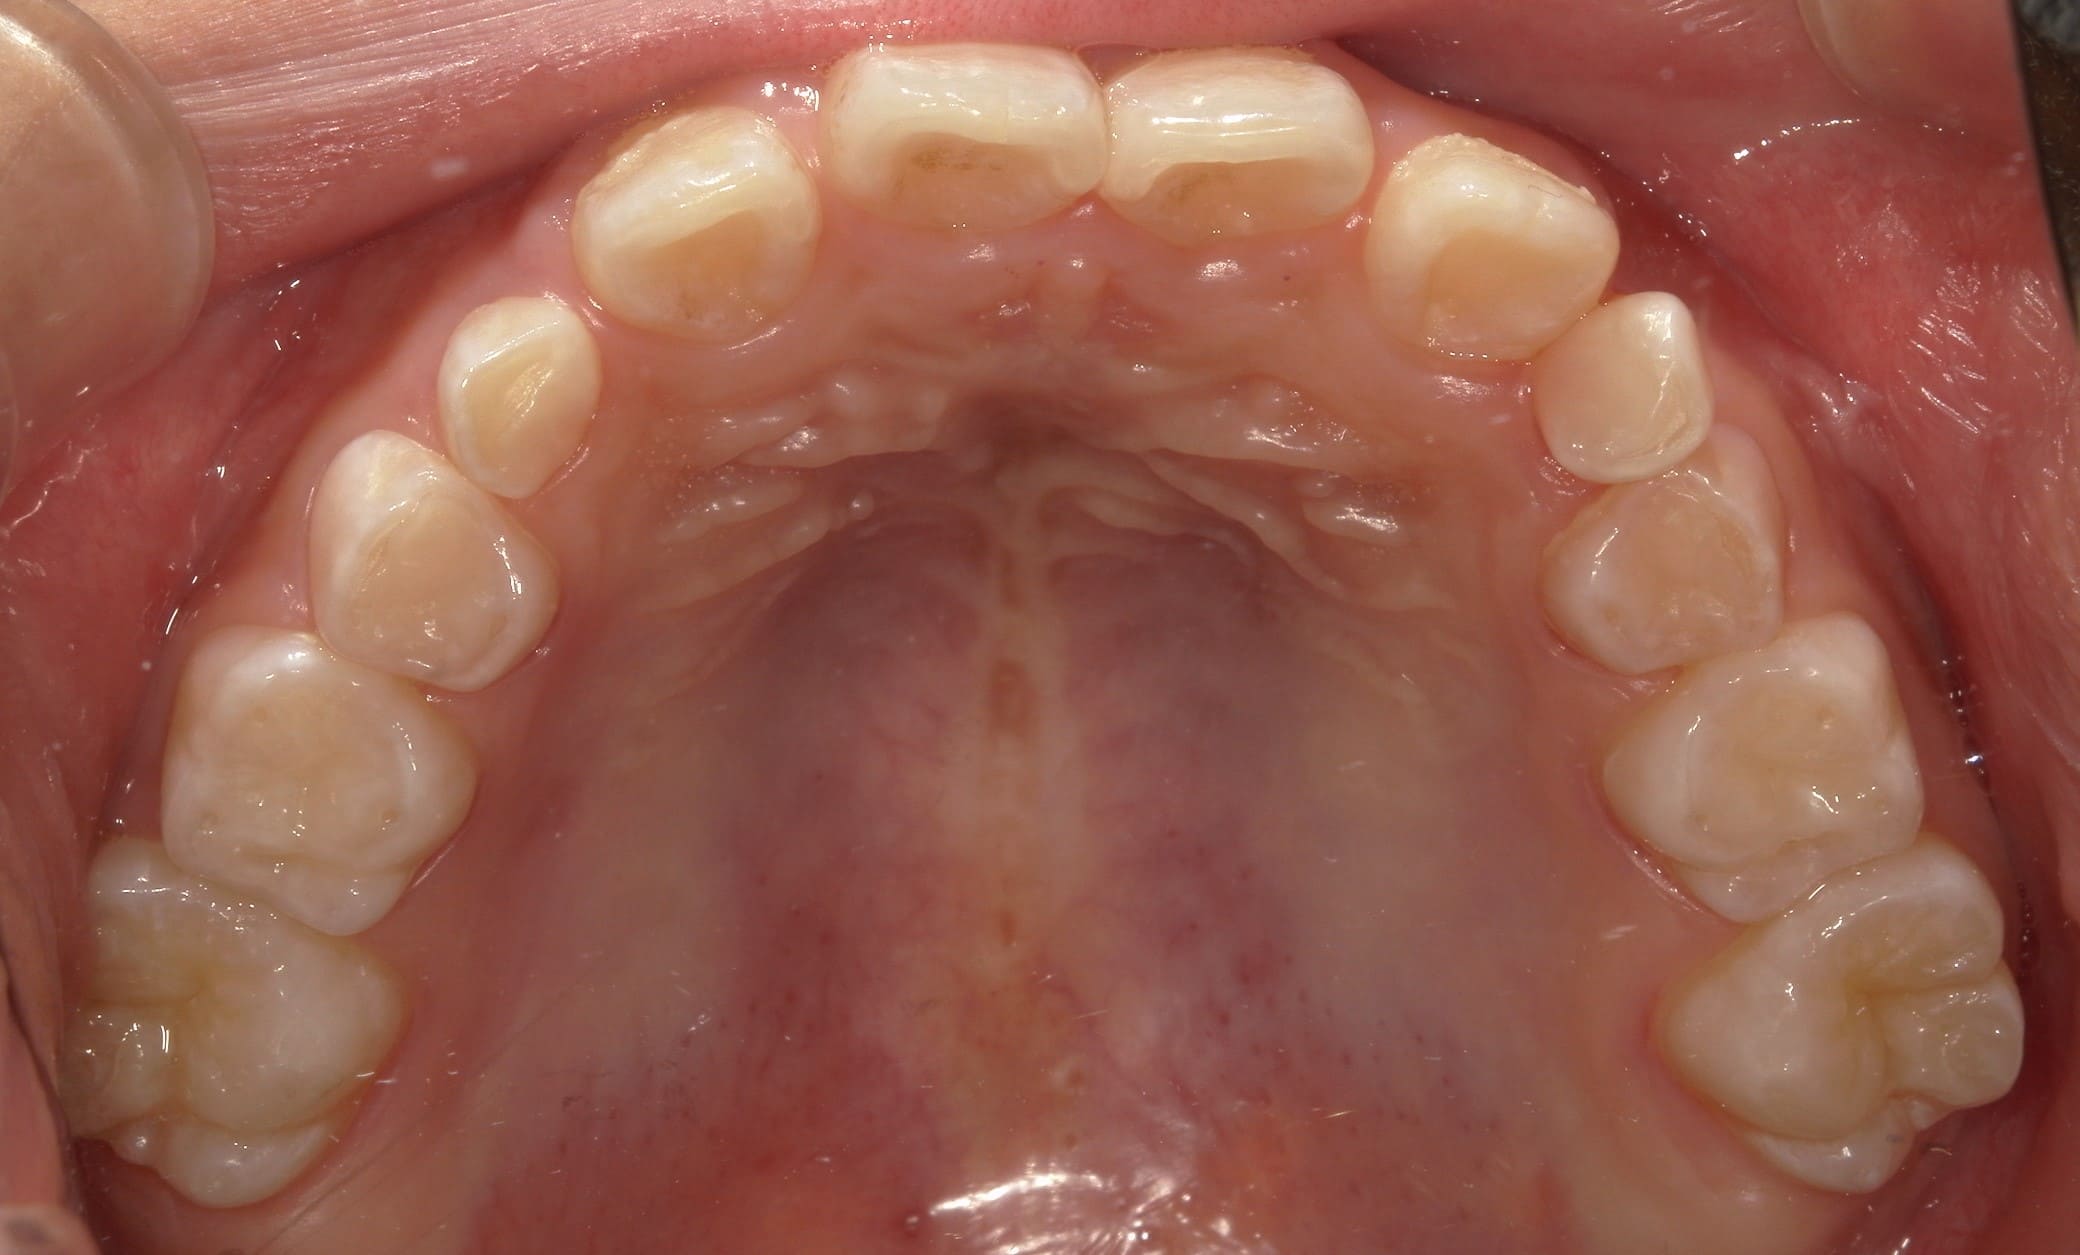

| 年齢・性別 | 8歳11ヶ月の男児 |

|---|---|

| 主訴 | 上顎の永久歯の位置がおかしいとのことで来院。萌出していない右上の前歯の状態に不安を抱えられていました。 |

| 治療期間・回数 | 約3年2ヶ月 |

| 費用 | 440,000円(税別) |